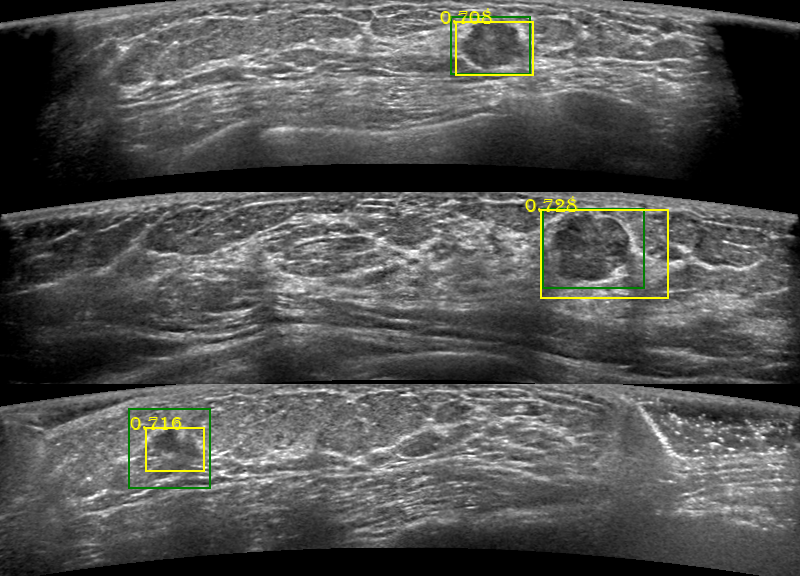

Fig. 3 shows three lesion detection results. Fig. 4 shows the sensitivity of our network to different sizes of lesions. For lesions smaller than 2 cm3𝑐superscript𝑚3cm^{3}, our network achieved a sensitivity above 95%; and when the lesion sizes was larger than 4 cm3𝑐superscript𝑚3cm^{3}, the sensitivity is 100%

Refer to caption

Figure 3: Example of lesion detection results. The areas in green boxes are the labels by doctors. The yellow boxes are model predicted with prediction probability values.